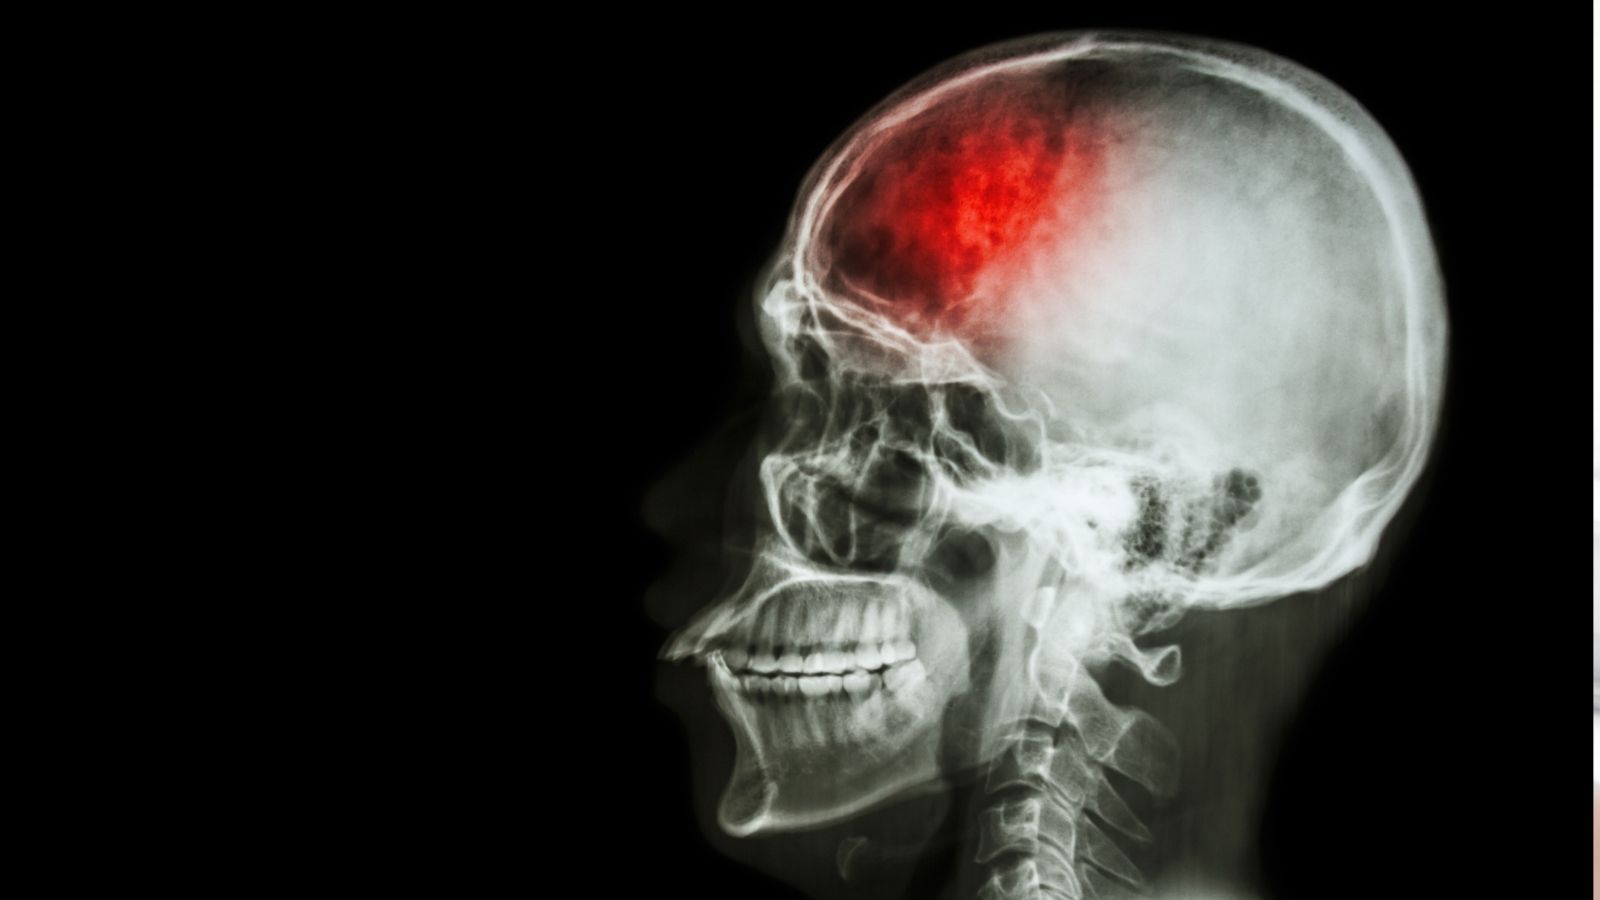

Udar to nagłe zaburzenie krążenia mózgowego, które prowadzi do niedotlenienia i obumierania komórek mózgu. Wyróżnia się przede wszystkim udar niedokrwienny (powodowany zatkaniem naczynia) i udar krwotoczny (wynikający z pęknięcia naczynia).

Analiza 26 badań z różnych krajów pokazała bardzo wyraźny i niepokojący wzorzec: w młodszej grupie wiekowej, czyli u osób poniżej 55. roku życia, udary pojawiają się coraz częściej, i to w tempie szybszym niż u osób starszych. Badacze zastosowali specjalny wskaźnik porównawczy (RTTR), który pozwala ocenić, jak różnią się trendy zachorowań w obu grupach. Jego wartość wyniosła 1,57 — co oznacza, że wzrost liczby udarów wśród młodych przebiega wyraźnie mniej korzystnie niż u osób powyżej 55 lat.

Co ważne, zjawisko to jest obserwowane niezależnie od rodzaju udaru. W przypadku udaru niedokrwiennego tempo wzrostu było jeszcze wyższe, natomiast w krwotoku śródmózgowym i podpajęczynówkowym również zauważano podobne, choć nieco mniej wyraźne tendencje. Zarówno kobiety, jak i mężczyźni wykazywali podobne wartości, co podkreśla, że rosnące ryzyko nie jest przypisane do konkretnej płci.